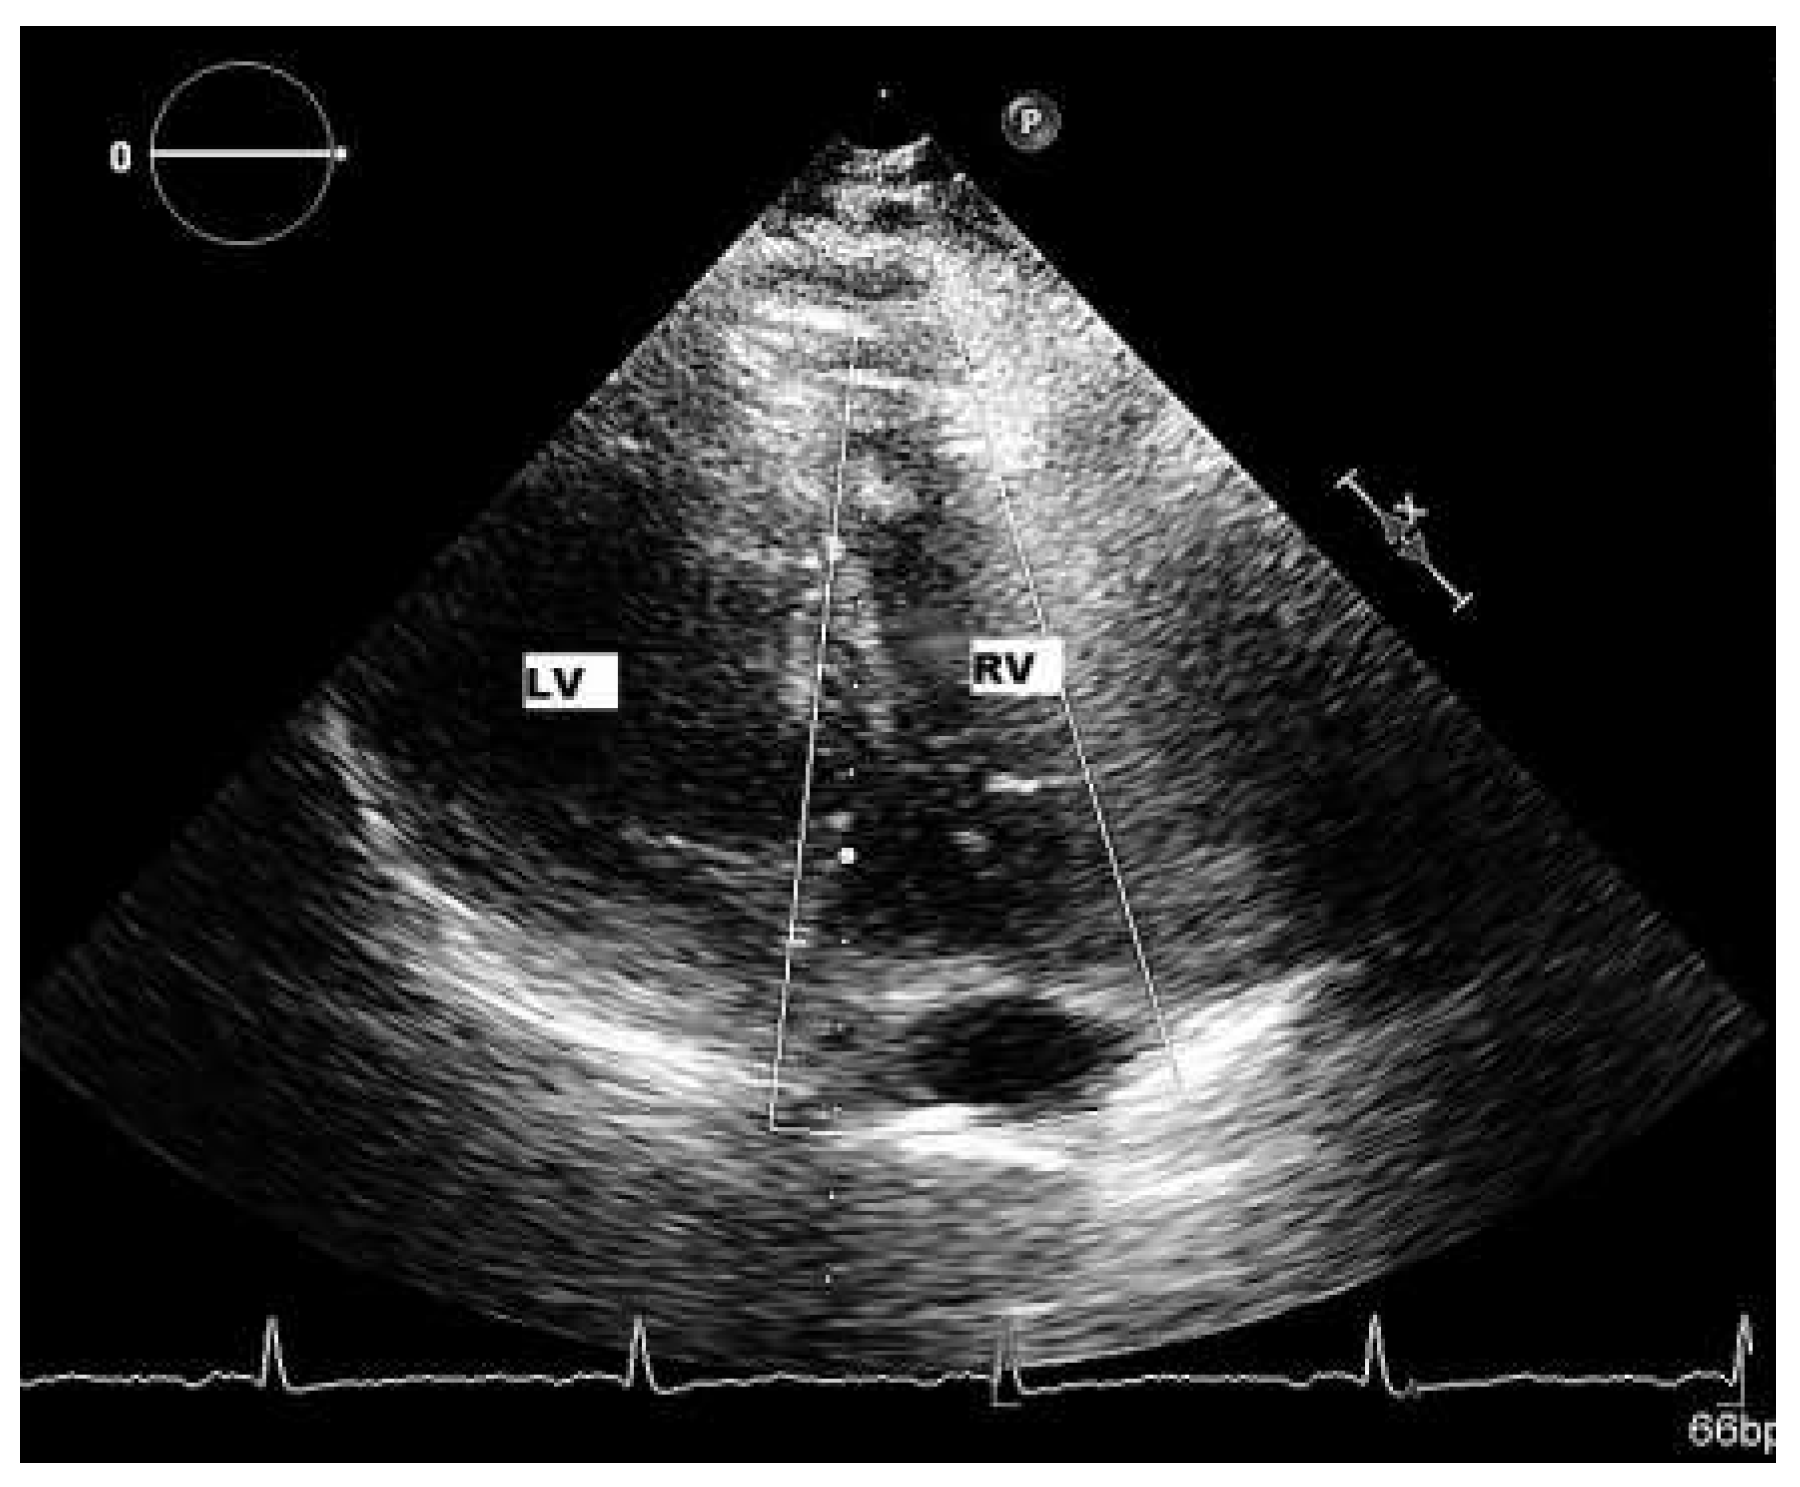

Patient

Six-month follow-up

Sixteen-month follow-up